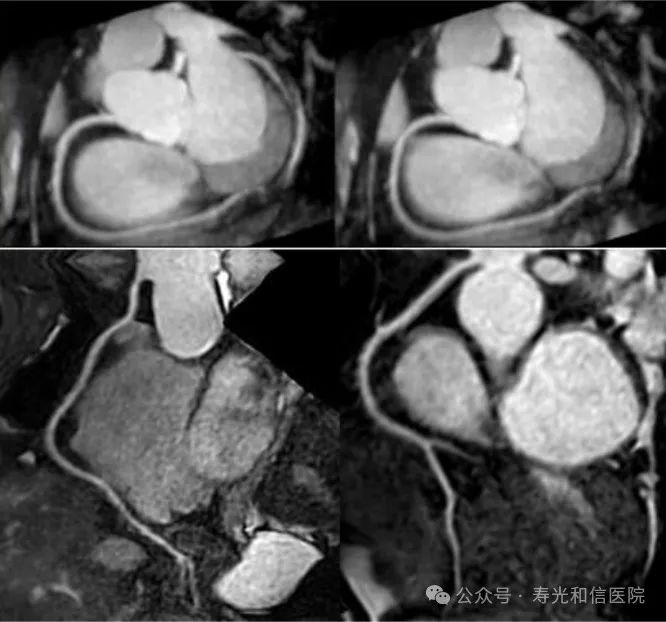

飞利浦大孔径光速Ingenia 3.0T核磁共振是业内唯一同时具备"全数字高清成像平台和四维多源射频发射成像平台"的高端3.0T核磁共振,具有病人检查舒适,扫描速度快,图像分辨率高的特点。在神经系统、骨肌系统、体部系统包括心脏和腹部等都有良好的应用和独到优势,为疾病的诊断及治疗提供更可靠、更丰富的信息,对于脑卒中和胸痛等中心的建设起到重要的作用。设备具备飞利浦独有的全数字线圈,可以实现三维全心不打药冠脉成像,无电离辐射和造影剂过敏风险,精准显示冠脉狭窄,有效排查临床无意义的冠脉狭窄(准确度达90%)。

3D 全心无造影剂冠脉磁共振成像

磁共振冠状动脉检查无辐射,无需对比剂,对于缺血性心脏病,可以一次成像完整显示全心冠脉,便于直观诊断冠脉各分支情况。